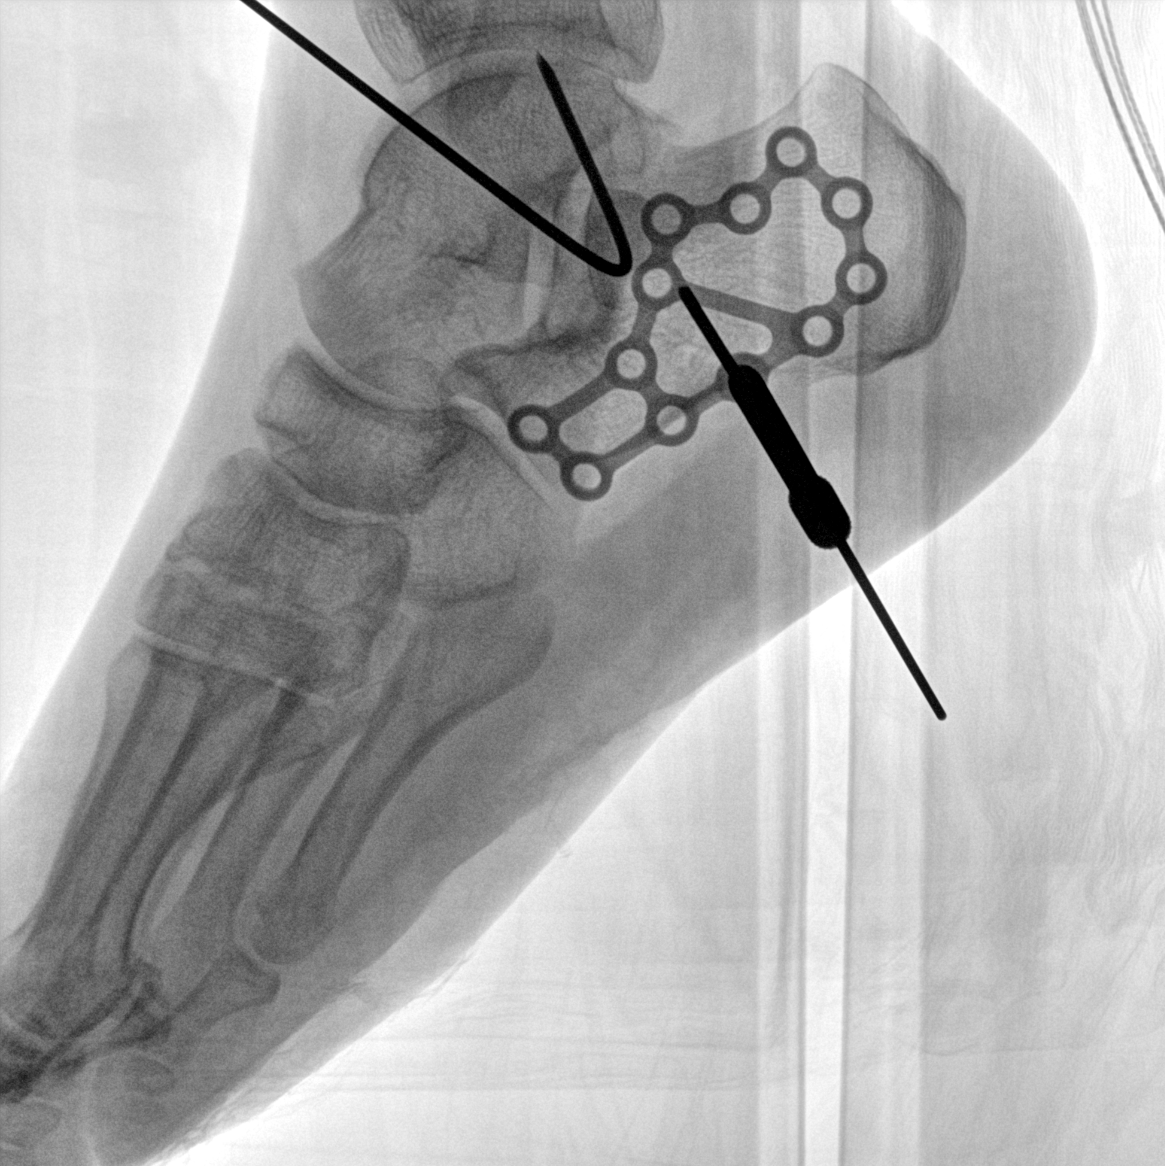

術(shù)中三維成像和橫斷面圖像提供多角度的手術(shù)診斷信息,輔助醫(yī)生進行術(shù)中評估判斷,諸如骨折復位情況和內(nèi)植入螺釘?shù)某叽绾臀恢茫o助手術(shù)更好地完成。

在C臂掃描過程中,始終保持拍攝主體處于射線束的中心,避免了序列圖像采集過程中的橫縱方向運動,減少相對運動造成的運動偽影。

平板垂直升降運動 便于術(shù)中微調(diào)平板與拍攝主體的距離,更加貼近病灶體,成像范圍更大,圖像更清晰。